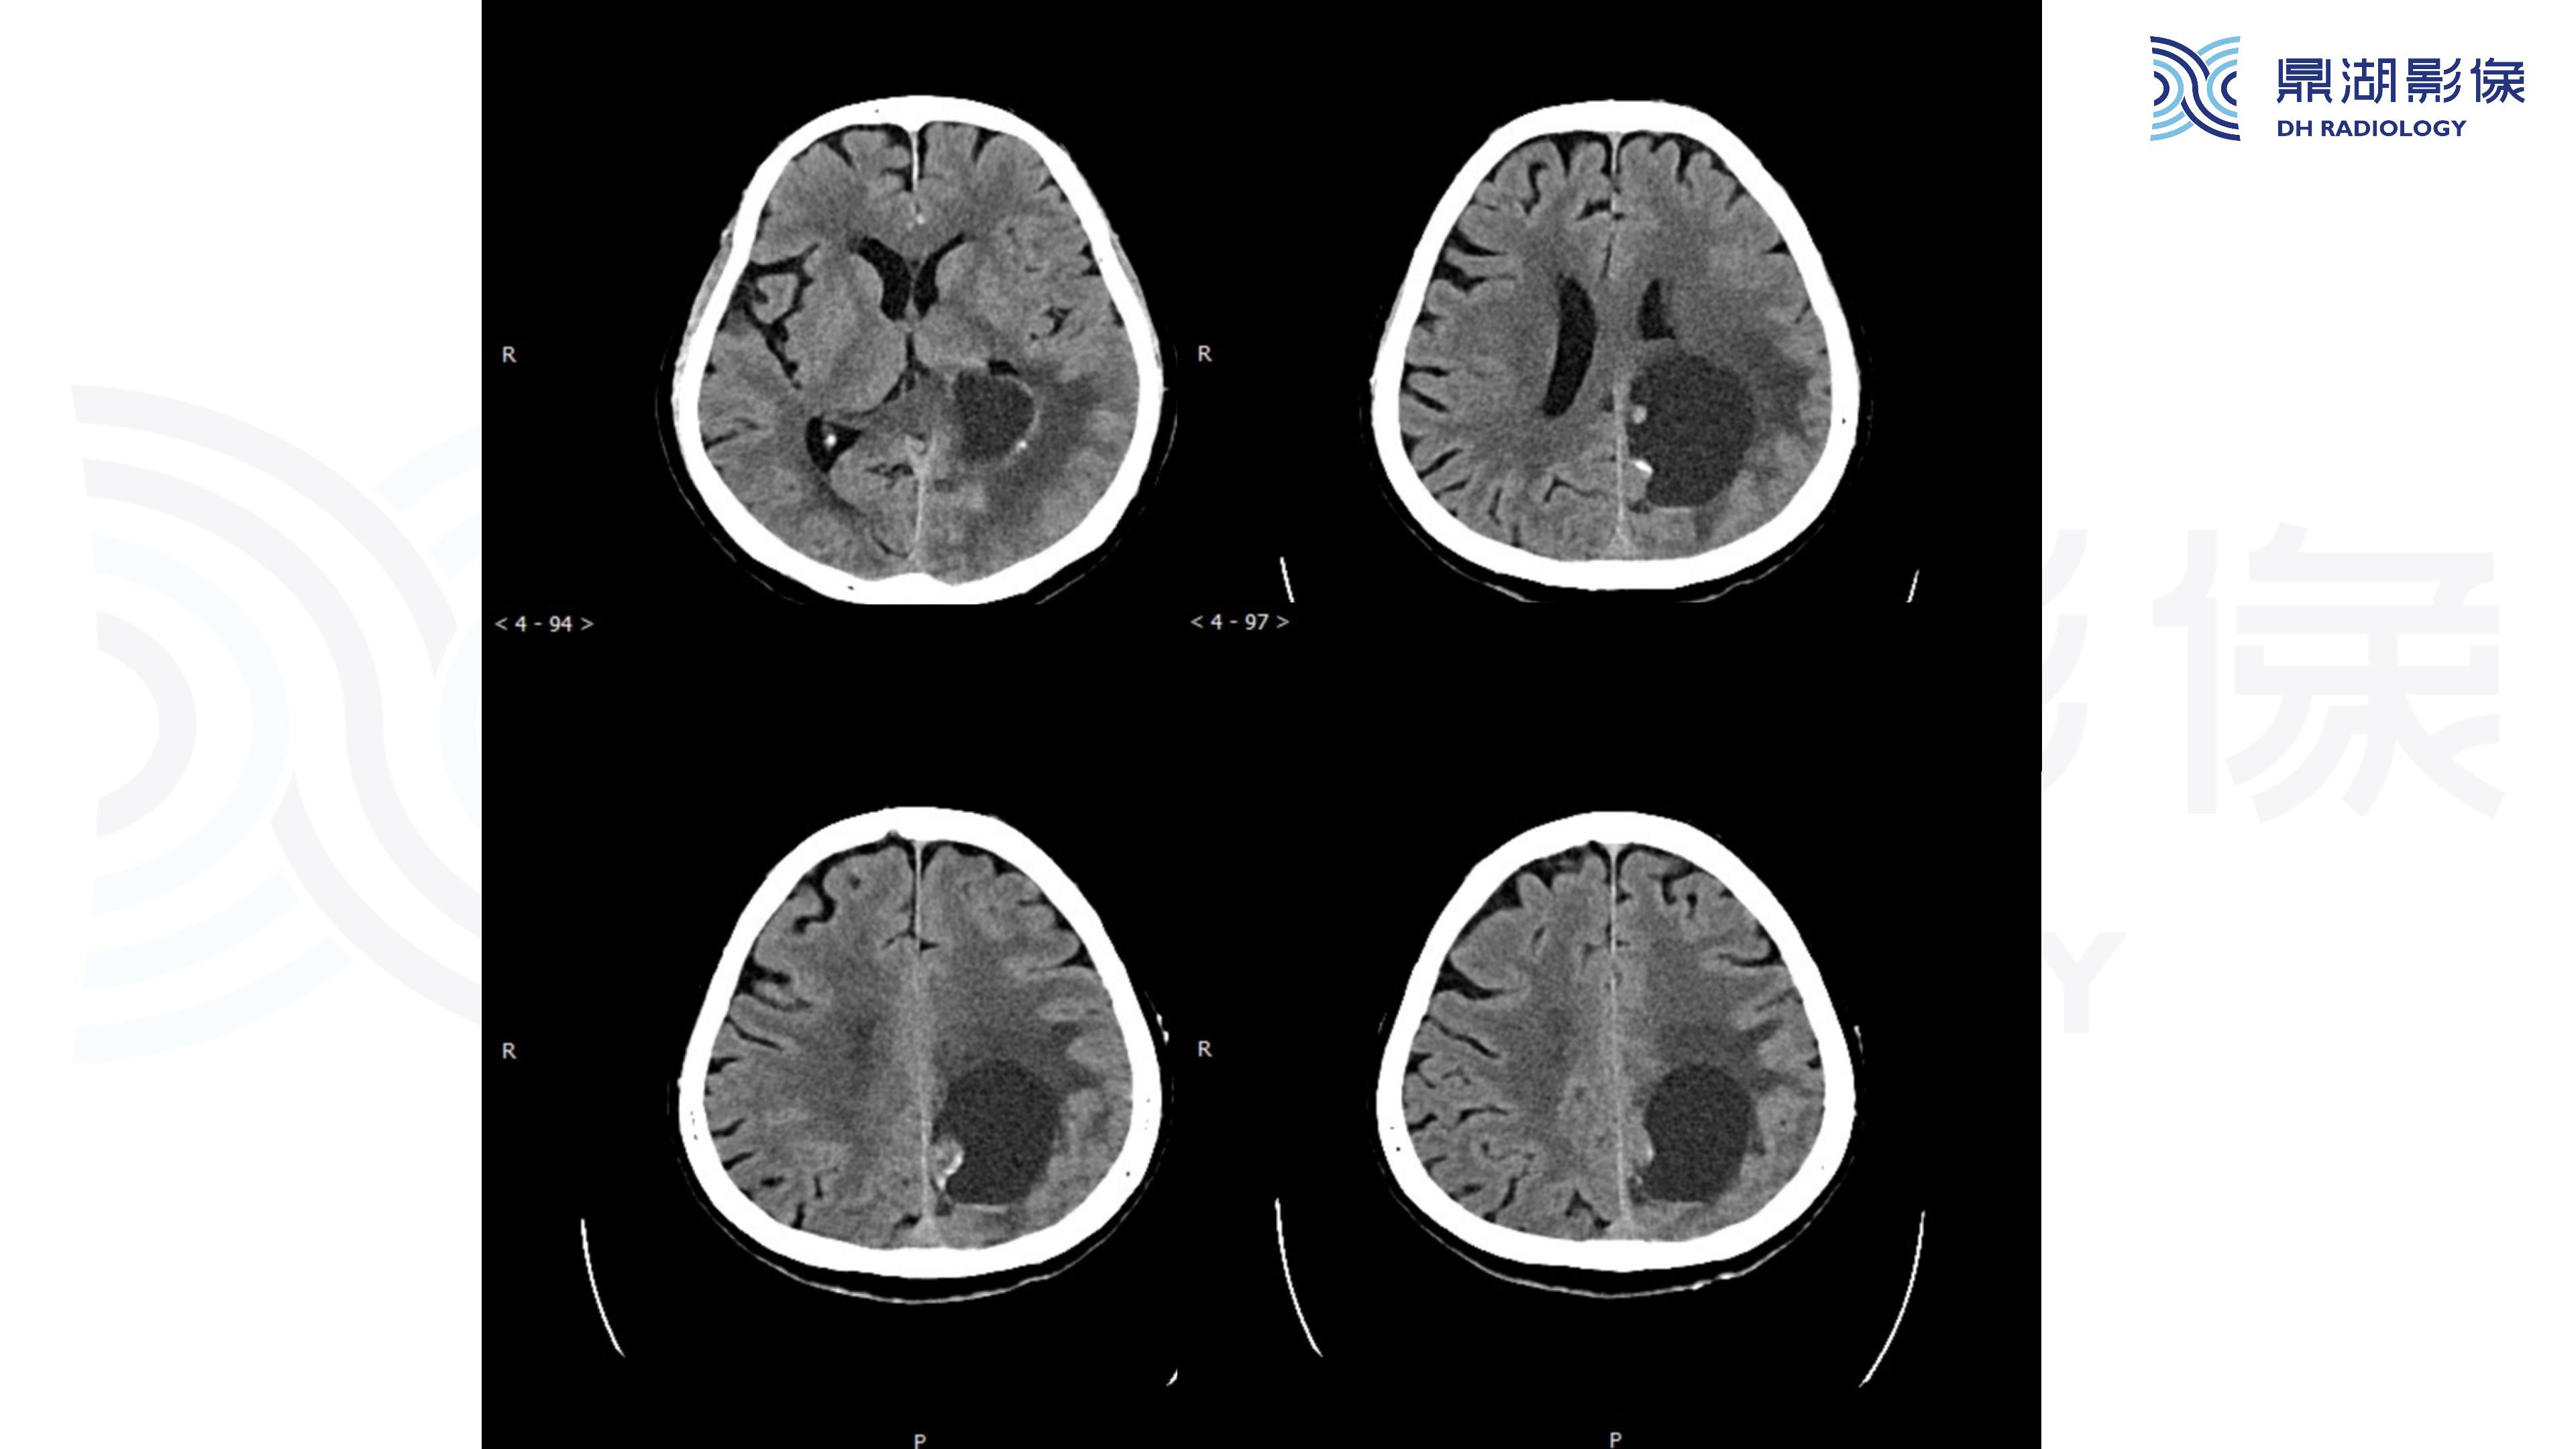

幕上毛细胞型星形细胞瘤(WHO Ⅰ级)